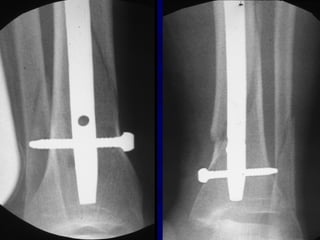

• 63.

Reduction of DistalTibial Fractures • Distractor • Joy Stick • Fibular Plating • Calcaneal Traction

Proximal and DistalCases Courtesy of R. Winquist M.D. Seattle, Wa.